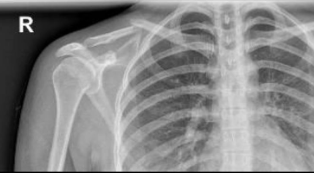

Hey there. I am Bailey Heaton's mom. A week ago, Bailey was headed home on their bike after taking care of some things at their old apartment when they were involved in a hit-and-run by a man on an e-scooter going the wrong way on a one-way bike path. The man t-boned Bailey, never stopping, causing them to fly off their bike. In the fall, Bailey's collarbone broke. We are fortunate that there weren't any worse injuries. Because of that, Bailey was released with a "mildly displaced clavicular fracture." However, in the last week, the fracture has shifted, becoming unstable, and now it requires surgery to repair it.